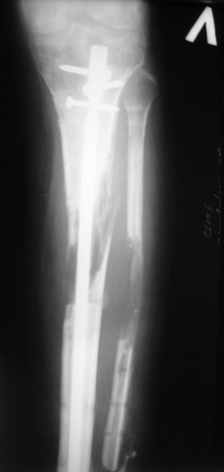

|  |  |  |  status localis на 14.11.08 (В ране визуализируется сухожилие.) | Больной А, 40 лет, находится в клинике с 15.10.08 с диагнозом: Сочетанная травма. Ушиб головного мозга лёгкой степени тяжести. Компрессионные переломы тел 12 грудного и 5 поясничного позвонков без неврологических осложнений. Закрытый внутрисуставной многооскольчатый перелом дистальных метаэпифизов обеих костей правой голени со смещением. Открытый внутрисуставной многооскольчатый перелом дистальных метаэпифизов обеих костей левой голени со смещением (см. Р-граммы). Хронический алкоголизм. Доставлен СМП после падения с 5-го этажа (не суицид). При поступлении состояние тяжелое. Глубокое оглушение. Дыхание самостоятельное, адекватное. Гемодинамика стабильная. По внутренней поверхности левой голени, в нижней трети, рвано-ушибленная рана 10-6 см, из раны выстоит проксимальный отломок большеберцовой кости, рана обильно загрязнена землёй. Интенсивная терапия в условиях реанимационного отделения, вытяжение за правую пяточную кость, параартериальная блокада обеих нижних конечностей, гипсовая лонгета на левую нижнюю конечность, ас-повязка на рану. Через 4 часа после поступления оперирован: после неоднократного промывания раны тёплой проточной водой с мылом, антисептиками, при ревизии определяется земля в канале проксимального отломка на глубину 3 см..., отсутствие надкостницы на концах дистального и проксимального отломков на 3 см. Удалено значительное количество мелких костных фрагментов, перемешанных с землёй, выполнена ПХО раны, резекция проксимального конца большеберцовой кости на 3,5 см, ЧКДО аппаратом Илизарова. Рана не ушивалась. В последующем перевязки раны с "Левомеколь", через 3 недели с момента травмы в ране определялись грануляции, нежизнеспособный конец дистального отломка. 10.11.08 ВХО раны, резекция дистального отломка на 3 см, перемонтаж аппарата наружной фиксации (см. Р-граммы). Отломки сближены на 2 см (остеотомию малоберцовой не делали). В настоящее время (5 сутки после операции) незначительное количество серозного отделяемого из раны, имеется дефект кости 4 см (см. Р-граммы). В последующем склоняемся к перемонтажу аппарата наружной фиксации, остеотомии малоберцовой кости в области повреждения, сближении отломков. По заживлению раны удлинение левой голени на 4 см. Однако, некоторыми высказывалось мнение о необходимости артродеза. Представляем рентгенограммы левой голени при поступлении, после повторного оперативного лечения и фото st.localis на 14.11.08. Будем очень благодарны за критику, комментарии, пожелания и мнения о дальнейшей тактике лечения.

Мы обычно не фиксируем малоберцовую кость. Просто стараемся сопоставить ее концы за счет хорошей репозиции. В представленном случае имеется некоторое смещение дистальных фрагментов кнаружи, и, как мне кажется, ротация их вместе со стопой кнутри (ротация хорошо заметна на прямом снимке по форме таранной кости и на боковом по соотношению отломков малоберцовой). Если это действительно так, то это несложно сейчас постепенно устранить в аппарате. И тогда концы малоберцовой кости будут находиться поближе друг к другу.

Ерсин, мы тоже имеем опыт такой фиксации. Подобную операцию за последние 3 года мы сделали трем пациентам. Снимки одного из них я прилагаю.

К сожалению, ни в одном из этих 3-х случаев мы не получили удовлетворяющего нас результата. Очень трудно провести штифт, введенный антеградно ровно по центру таранной кости. Отсутствие подвижности между диафизом и дистальным отломком большеберцовой кости (после фиксации в аппарате в течение 1-2 мес) очень усложняет проведение штифта в центр блока таранной кости. Поэтому мы от этого пока отказались, и проводим штифт через пятку. При данном варианте фиксации подобных проблем не возникало ни разу.